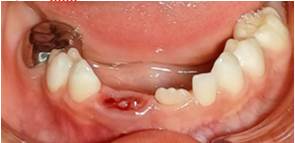

Al examen clínico intraoral, con espejo bucal y luz artificial en el sillón dental se destaca la presencia de dentición primaria con acúmulo de biofilme, lesiones cariosas cavitadas en molares primarios, la presencia de dos dientes supernumerarios: uno en el sector anterosuperior izquierdo y otro en el sector anteroinferior, fusionado con el incisivo central y el lateral derecho con dos surcos verticales en la superficie labial y lingual en la unión de las piezas dentales, sin presencia de lesiones cariosas y con un periodonto circundante sano. En la sección anterior superior se presenta mordida cruzada anterior de una pieza dental y a nivel de mandíbula se observó leve giroversión del central primario izquierdo y de las piezas fusionadas (Figura 1 A, B y C).